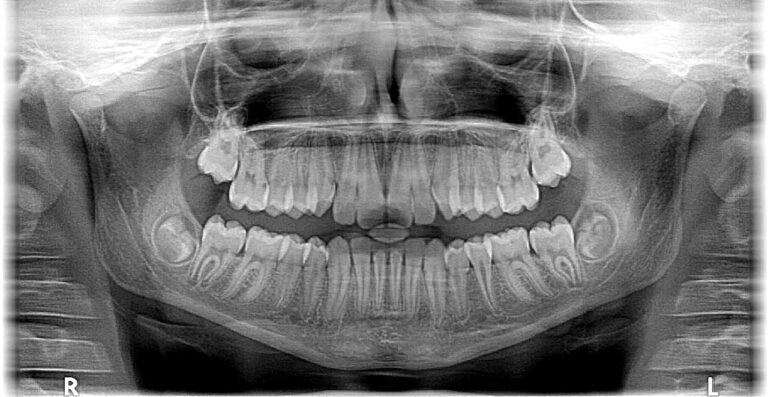

Dental X-rays are used during routine dental exams for a variety of reasons. Dental X-rays are used on adults to look for areas of decay that are not visible to the naked eye. For example, your dentist will be able to see the areas between the teeth and underneath a filling by using a dental X-ray. X-rays can also help detect early signs of tooth decay, observe overall oral health, and monitor jaw and tooth formation for adolescents.

This practice allows dentists to exercise preventative action by discovering problems such as bone loss from periodontal disease, signs of issues in the root of the tooth, infection or death of the nerves, cysts, cancer, or changes caused by disease of the body. If your dentist plans to place braces, dentures, tooth implants, or other dental work they will also use dental X-rays to assist them in this preparation.